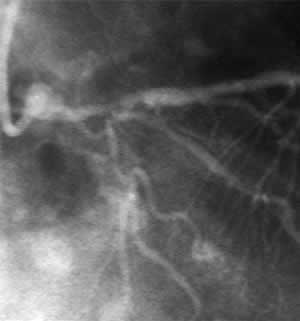

| Final CAG Findings:'01.10.4 LVG: asynergy (A&L), EF: 55% CAG: #5 50%, #7 90%, #9 99%, #11 75% HL 100% (collateral from LAD) |

DCA for HL Branch Stenting for LAD 3.5mm/18mm |

I-5 : 3 months follow-up angio